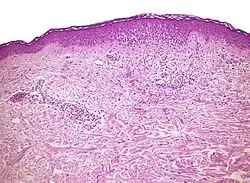

| Mycosis fungoides | Present | Focal | Regular or irregular | Normal | Normal | Minimal or no spongiosis; ±Pautrier microabscess | Atypical lymphoid cells lining the dermo–epidermal junction | ![]() |

Non vesicullobullous, non-pustular lesions without epidermal changes